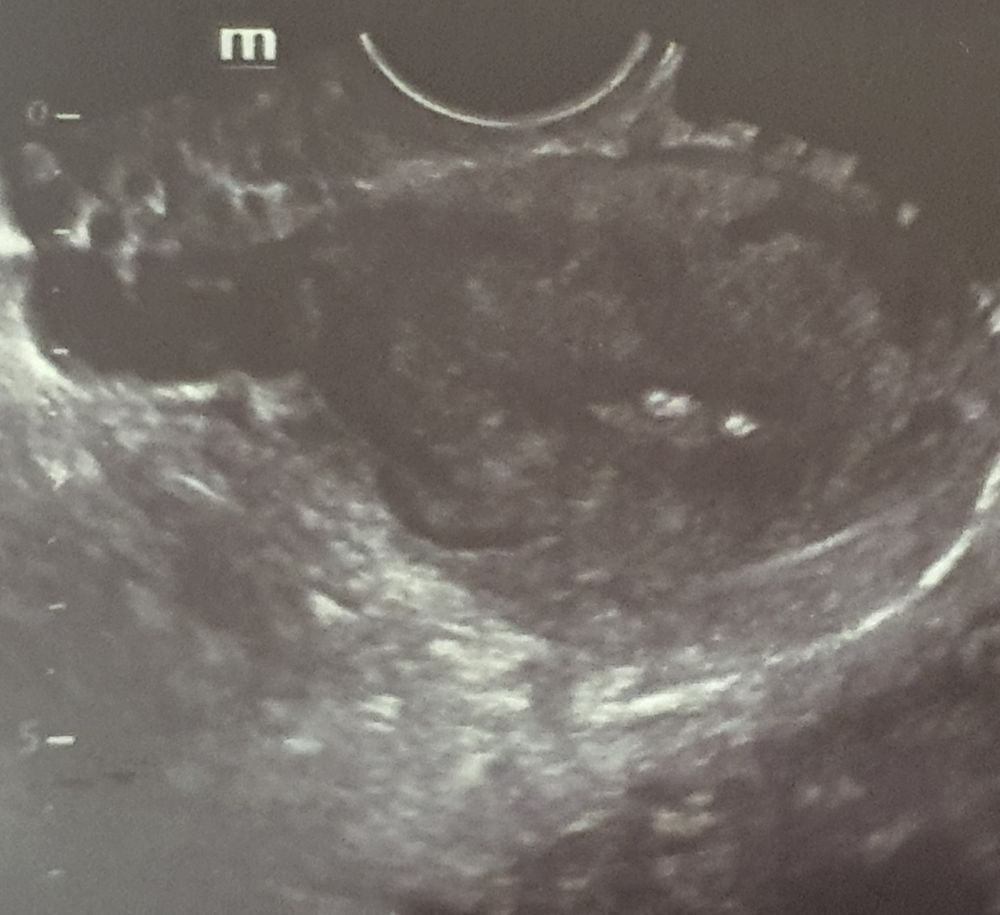

Беременность? Полип?

УЗИ на 5 недели. Персистенция фолликула?